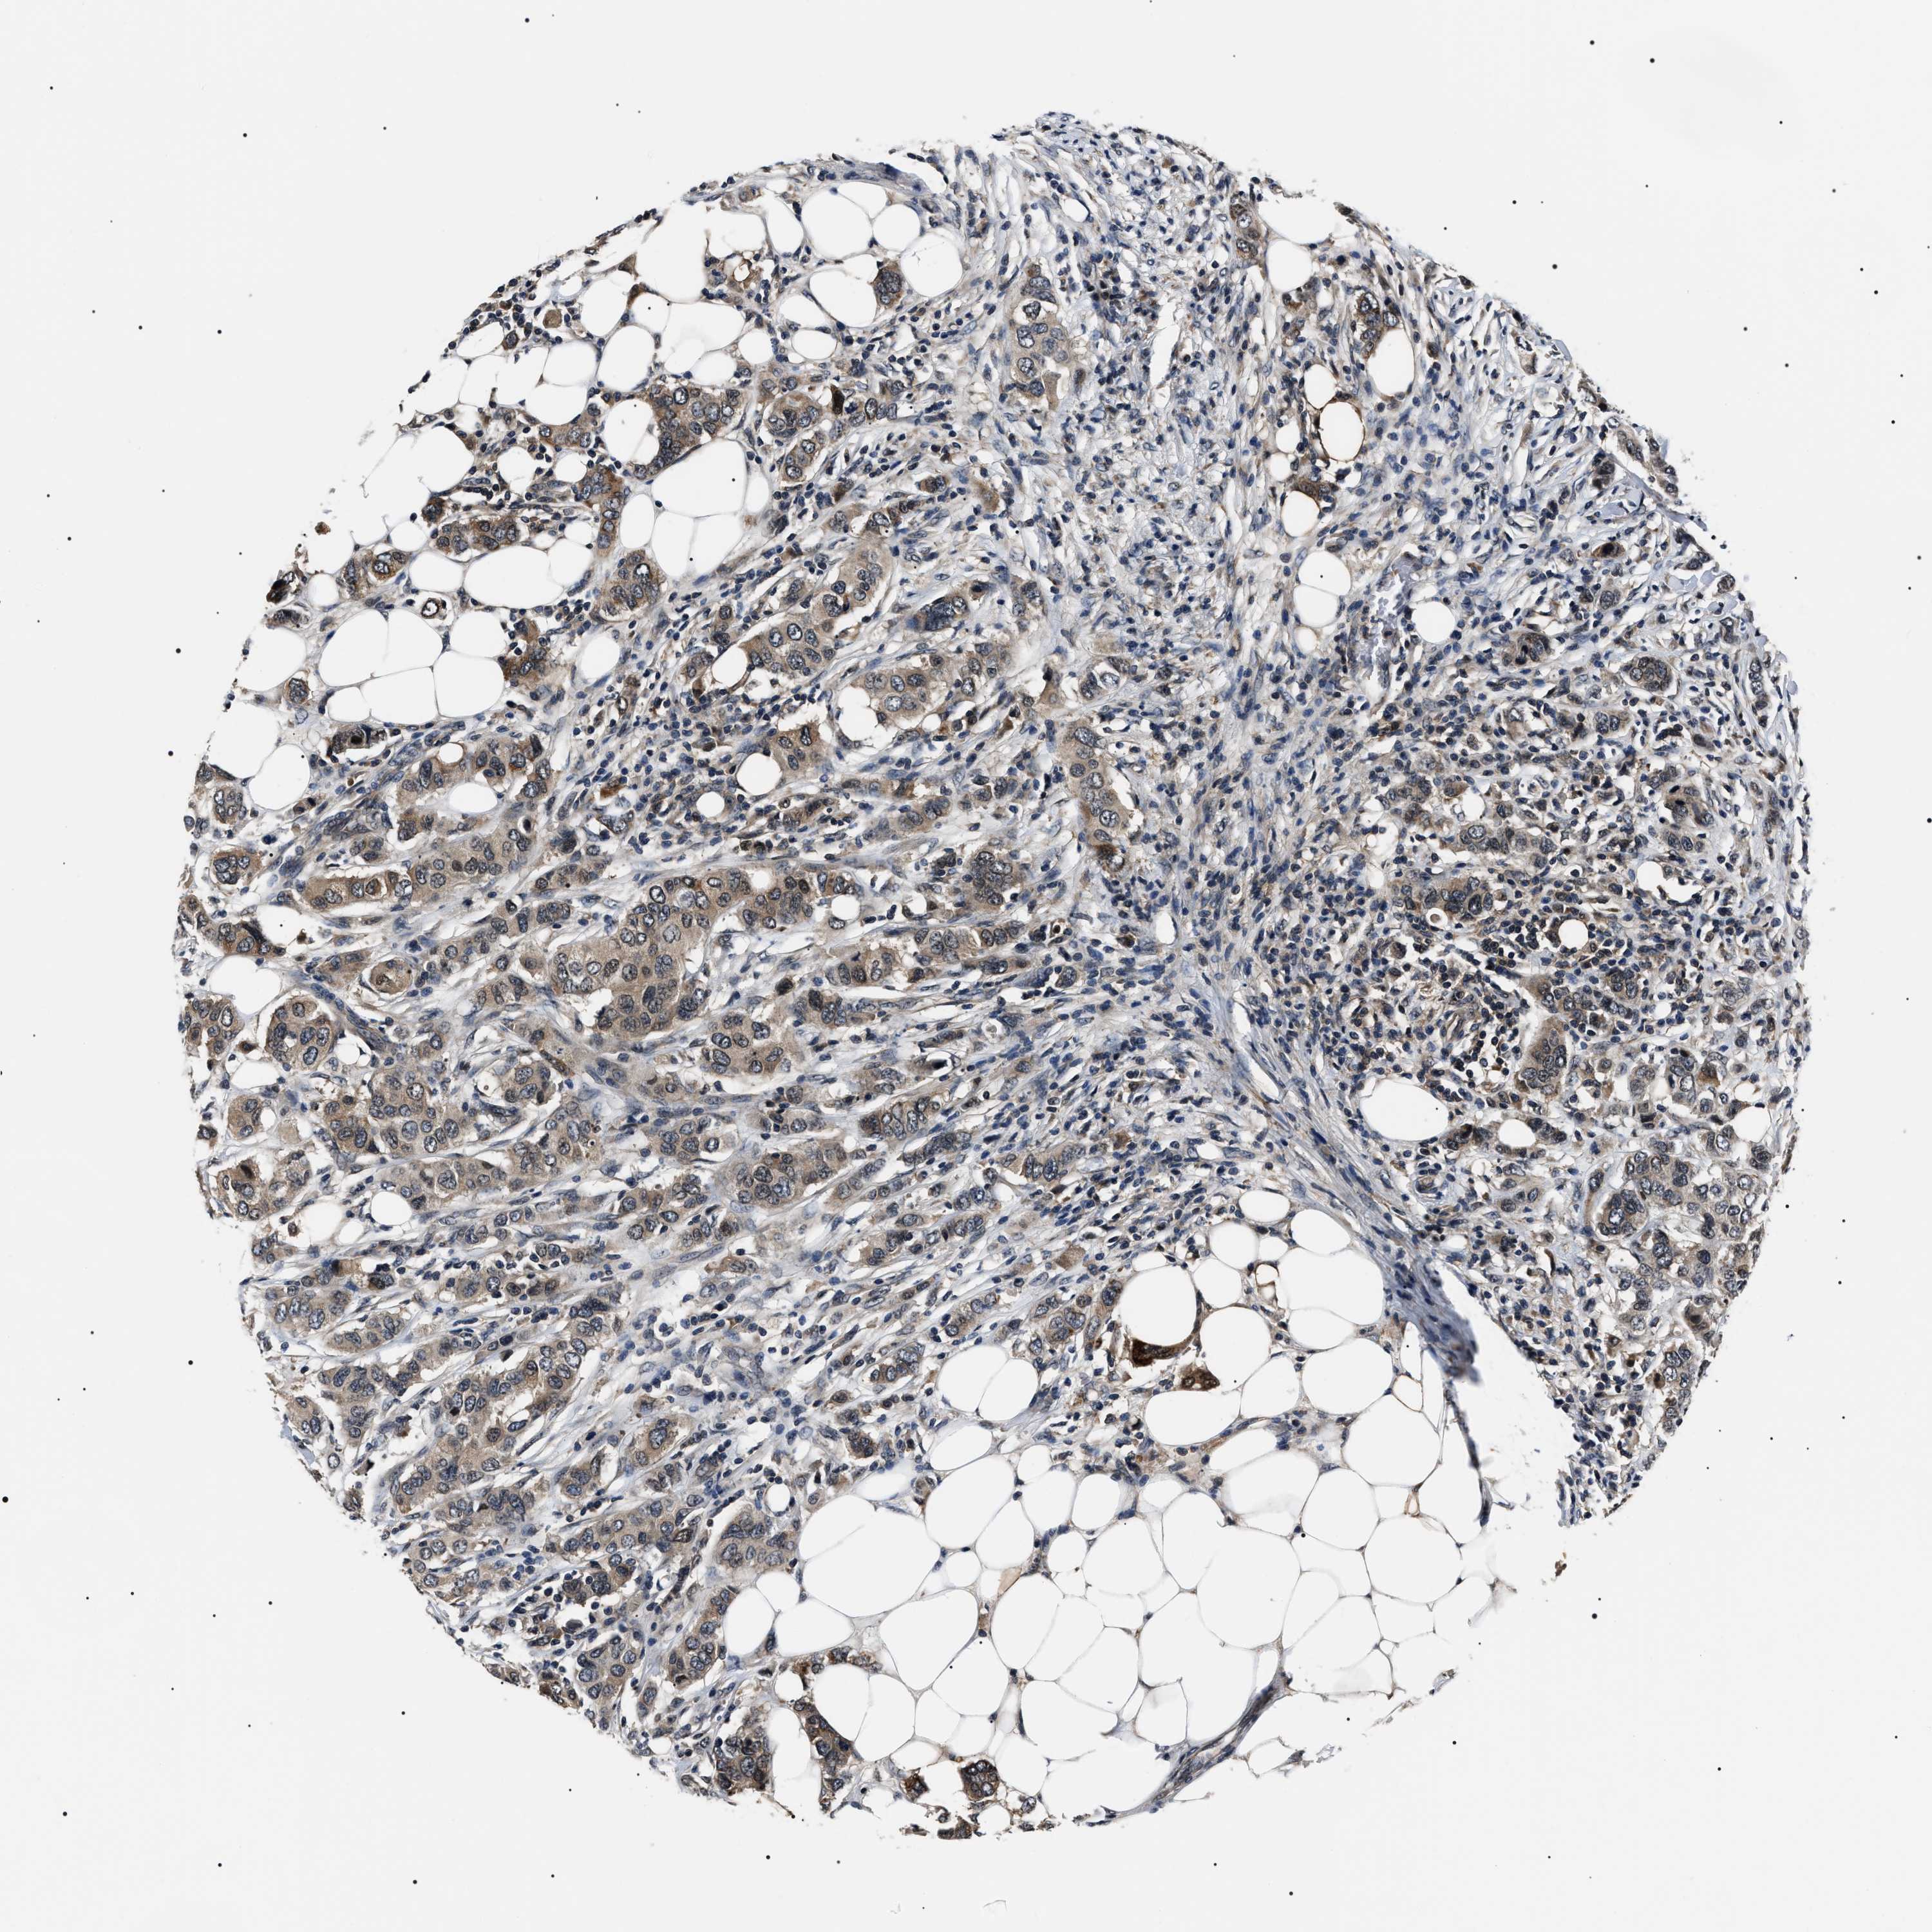

CANCER BREAST CANCER Show tissue menu

BRCA TCGA BRCA VALIDATION PROTEIN EXPRESSION

Breast cancer

Human cancer

Breast invasive carcinoma